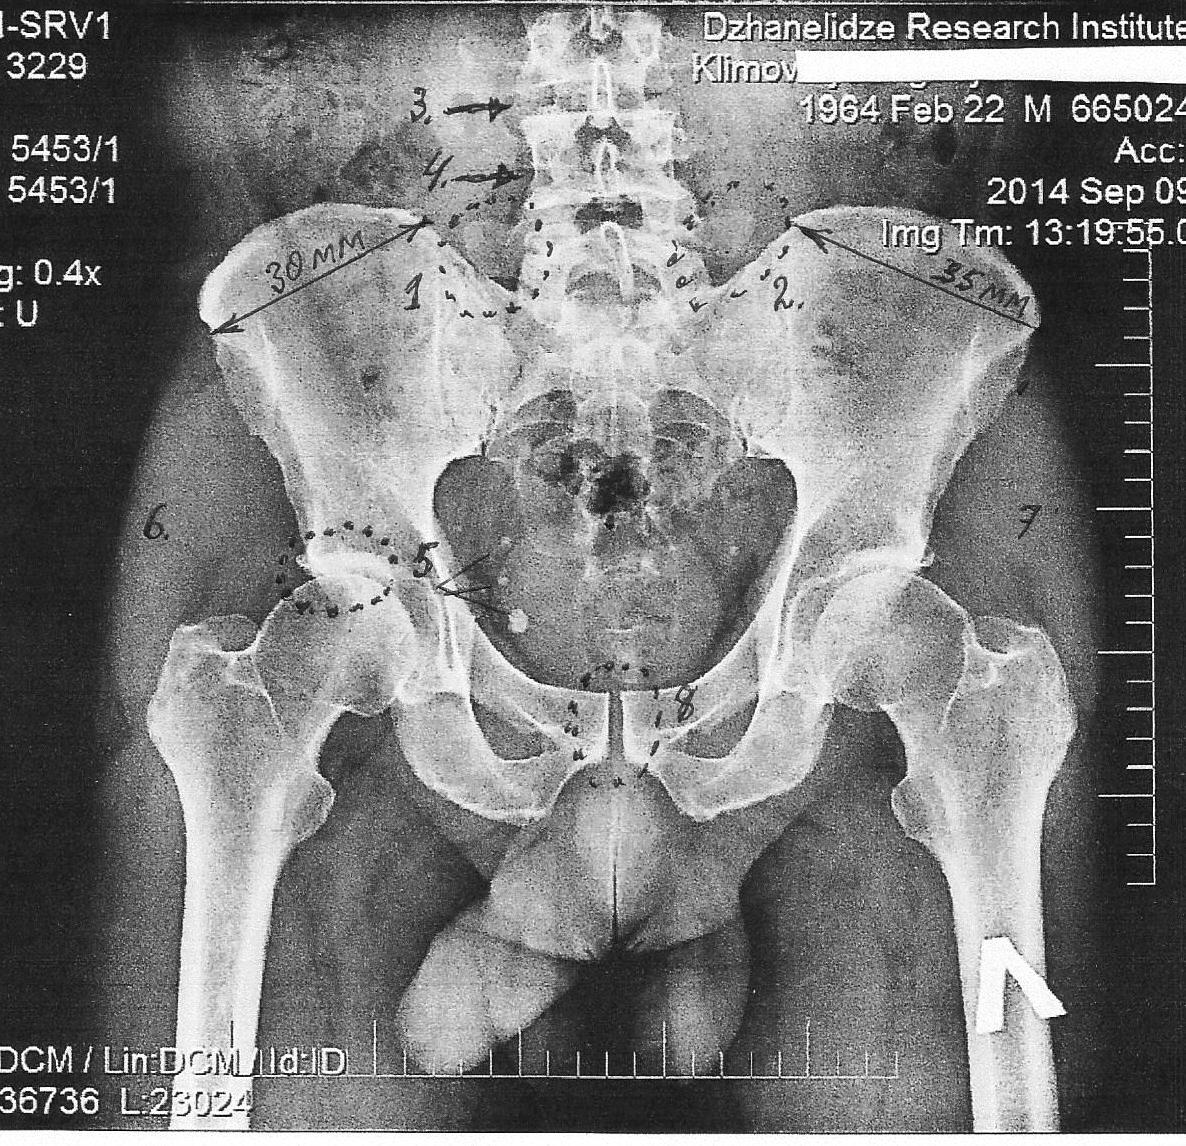

СНИМОК -1.

Начнём по порядку номеров, проставленных на снимке.

№1 и №2

Видны два поперечных отростка пятого поясничного позвонка. Особенность в том, что расстояние между его поперечными отростками и краями подвздошных костей не равновелики, и там, где стоит цифра «1» его практически нет, в отличии от противоположной стороны, тогда как в норме они должны быть одинаково удалены от края подвздошных костей.

Вопрос: - что заставило пятый позвонок а) – наклониться вправо? (левая часть таза отмечена маркером «Л» на левой бедренной кости) и б) - ротироваться влево, относительно своей оси?

Ответ: - мышцы. Это, прежде всего, мышца между правым поперечным отростком и краем подвздошной кости. Она от хронического перенапряжения и укорочения наклонила вбок тело позвонка. Естественно, что ей в этом помогали и другие мышцы позвоночного столба, например, ротаторы.

№3 и №4 (там, где №4 - стрелочку надо было опустить ниже, на уровень межпозвоночного диска L4 - L5).

На снимке видны пространства между телами позвонков, заполненные хрящевыми дисками. Обратите внимание, между 3 и 4 позвонками и 4 и 5 щели не равноценны по высоте, явно видно, что первая щель шире (значит и хрящ здесь полноценнее), тогда как между 4 и 5 она заполнена хрящём уже пропитанным солями кальция, то, что в «народе» называют – «остеохондрозом». Одна больная жалуется другой: «… у меня постоянно болит голова и я постоянно хожу к врачу. И всякий раз она говорит, ну что хотели, у вас ведь очень острый остеохондроз, и все ваши боли от него!» Врачи не должны быть «народом».

Если ещё раз присмотримся к телам позвонков, то увидим, щель (расположена справа) между суставными отростками пятого и четвёртого поясничных позвонков, которой не должно быть: пятый позвонок наклонён в левую (на снимке) сторону, что хорошо видно даже по направлению его остистого отростка.

№5 (следует вернуться к рисунку – 1)

Пациент обратился за помощью по поводу болей в пояснице и, частично, в области верхней трети правого бедра. На снимке в области №5, обведённой пунктиром, видна своеобразная «губа» в виде утолщённого края верхней части вертлужной впадины подвздошной кости, да ещё «окрашенной» белым цветом – рентгенологический признак избыточного количества извести в этом месте, месте наибольшего напряжения - вес тела опирается на эти зоны(!).

Присмотревшись, можно увидеть выступающий в сторону шип – остеофит, как признак того, что организм собирается «запечатать» (обездвижить) этот сустав, который также мог быть причастен к возникновению болевых симптомов у пациента.

На противоположной стороне, как видим, этот процесс тоже выражен, однако не так сильно.

№6 и №7

Как уже писал ранее, на снимках магнитной (ядерной) резонансной томографии (МРТ или ЯМР) видны мягкие ткани. На этом снимке они также хорошо просматриваются, и для миологов (подчёркиваю – для МИОЛОГОВ!) они представляют особый интерес.

Обратите внимание, как по разному окрашены мышцы (№6 и №7), слева белый цвет интенсивнее и они (мышцы) массивнее (больше выдаются вбок, подобно сокращённому бицепсу на руке), и они более сокращены, чем справа. На процедуре мною было выявлено возвышение правой ягодичной области над левой, а снимок подтвердил этот факт по своему.

Чтобы это могло означать? Только одно – мышцы слева больные! В них больше накопилось солей и шлаков. Это, прежде всего, малая и средняя ягодичные мышцы, а ближе к наружному вертелу ещё и напрягатель широкой фасции бедра.

Однако, и это ещё не всё! Не смотря на то, что я не сказал о таких «неприятных мышцах для тазобедренного сустава, как группа приводящих мышц бедра (особенно – гребенчатая), за то член пациента своей головкой «указывает» нам на этот белесоватый мышечный тяж, как свидетельство его избыточной плотности и напряжения тканей этой мышцы.

Давайте вернёмся к №5. Это - особая «песня»! А что обозначают эти три белых точки? Уверяю - это не артефакты (дефекты на плёнке или бумаге). Правильно! Это петрификаты (где «petro» - камень, лат.)! То есть, конкретное отложение солей.

Предполагаю, что они содержат в себе соли молочной кислоты (лактаты) и соли кальция. И эти образования расположены в грушевидной мышце, она как раз берёт начало от поверхности крестца и крепится к большому вертелу бедренной кости. При укорочении, она способна стягивать и блокировать движения в тазобедренном суставе.

Я не упомянул про разные величины (ширину) подвздошных костей: 30мм и 35 мм (при естественной величине таза – они превращаются уже в сантиметры!), только потому, что правой (меньшей по величине) подвздошной кости жилось куда как хуже, чем левой, из-за того, что больные мышцы не справлялись с оттоком венозной крови от неё, оставляя тазовую кость на голодном пайке.